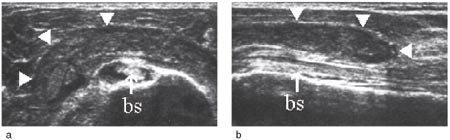

Vurdering av den lange bicepssenen med ultralyd er mer krevende enn vurderingen av rotatorcuffen. Dette skyldes stor interindividuell variabilitet og hyppige artefakter. Sammenlikning og kontroll av funnene med den kontralaterale siden er derfor påkrevd (8). Typiske funn ved tenosynovitt er enten hyper- eller hypotrofi av senen sammenliknet med motsatt side, redusert ekkogenisitet, ekkofattig halo rundt senen og hvelving av sulcustaket over rotatorcuffnivå (e-fig 11) (3, 9).

Subluksasjon og luksasjon av senen skjer vanligvis i medial retning, og er følge av en skade i det stabiliserende kapsulo-ligamentære apparatet i sulcusområdet. Her inngår musculus supraspinatus og subscapularis som viktige elementer, og bicepsseneluksasjon er derfor ofte kombinert med skade i disse delene av rotatorcuffen (e-fig 12) (1) – (3, 8).

Bicepsseneruptur finnes isolert eller i forbindelse med rotatorcuffruptur. Kriteriene for ruptur er avbrekk av den fibrillære senestrukturen i lengdesnitt (e-fig 13) og manglende senefremstilling i sulcus intertubercularis i tverrsnitt (1, 3).